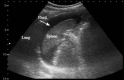

Figure 1

Morison’s pouch.